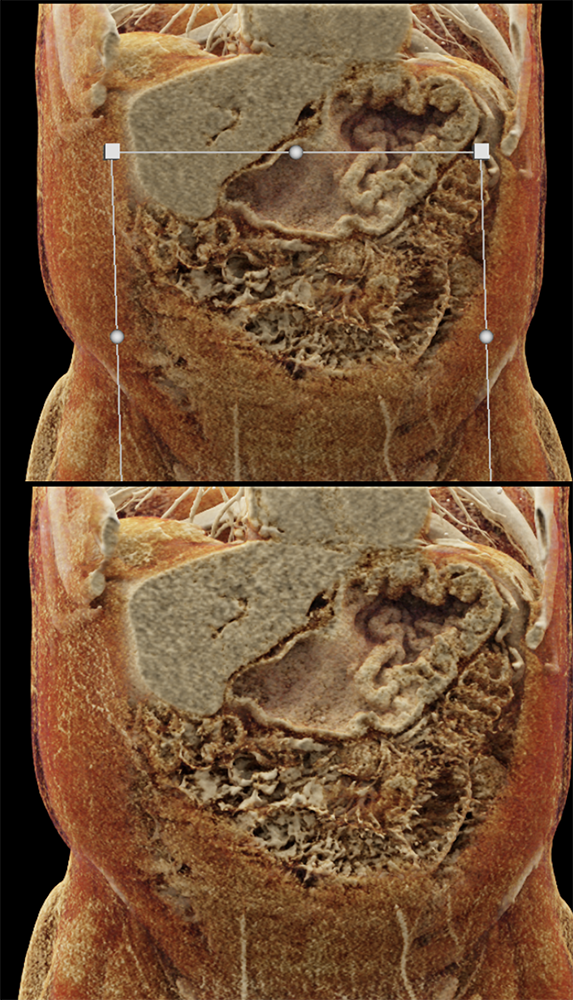

Watermelon stomach (WMS), or gastric antral vascular ectasia (GAVE) ![]() |

“Gastric antral vascular ectasia primanily affects women (9:1 female-to-male ratio) aged 56-76 years, and is associated with liver cirrhosis (37%) and achlorhydnia (35%). The usual symptoms are iron-deficiency anemia and melena due to chronic gastrointestinal bleeding from the dilated, superficial, and easily traumatized vessels. Antrectomy is curative, but endoscopic treatment with heat probes or lasers has shown promise.” Gastric antral vascular ectasia ("watermelon stomach"): radiologic findings. Urban BA, Jones B, Fishman EK, Kern SE, Ravich WJ. Radiology. 1991 Feb;178(2):517-8. |

“In our patient, the findings of prominent mucosal folds extending from the pylonic channel on upper gastrointestinal series and the thickened antral wall on CT scans correlate well with the known pathologic appearance of gastnic antral vascular ectasia. Histologically, antral thickening results from a combination of foveolar and fibromuscular hyperplasia. Grossly, the antral fold prominence appears to result from bunching of the mucosa in the thickened, hypercontractile antrum.” Gastric antral vascular ectasia ("watermelon stomach"): radiologic findings. Urban BA, Jones B, Fishman EK, Kern SE, Ravich WJ. Radiology. 1991 Feb;178(2):517-8. |

“Watermelon stomach (WMS), or gastric antral vascular ectasia, is an uncommon but clinically important cause of chronic occult or overt gastrointestinal (GI) blood loss. Patients typically present with symptomatic anemia and hemoccult positive stools. Although the diagnosis is based primarily on the typical endoscopic appearance, the lesion may be overlooked on initial evaluation or interpreted as "gastritis." Gastric biopsy may be helpful in confirming the diagnosis by showing vascular ectasia, typically without inflammation. WMS is idiopathic but is often associated with autoimmune diseases or cirrhosis of the liver. The majority of patients with classic WMS are elderly and female.” |

“Gastric antral vascular ectasia (GAVE) is a rare entity with unique endoscopic appearance described as "watermelon stomach." It has been associated with systemic sclerosis but the pathophysiological changes leading to GAVE have not been explained and still remain uncertain.” Gastric Antral Vascular Ectasia in Systemic Sclerosis: Current Concepts. Parrado RH et al. Int J Rheumatol. 2015;2015:762546. |